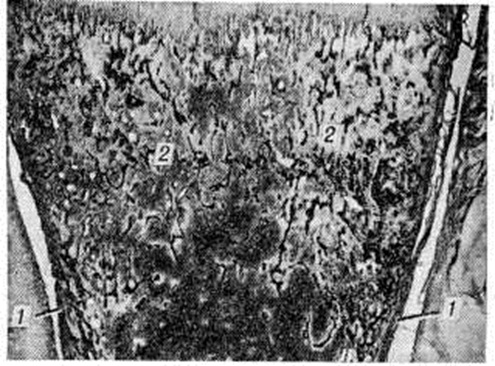

При позднем Остеогенез несовершенный макроскопически определяют обилие старых заживших переломов трубчатых костей и ложных суставов, а также значительные искривления позвоночника, костей таза и конечностей, обусловленные не только неправильным сопоставлением костных отломков в процессе заживления перелома, но и приспособительной перестройкой костей в условиях изменённой статической нагрузки. Например, при невозможности к передвижению в вертикальном положении больные приспосабливаются передвигаться на четвереньках или ползком, что приводит к значительному искривлению трубчатых костей верхних и нижних конечностей, а также костей таза. Кости отличаются необыкновенной хрупкостью и легко режутся ножом. На распилах длинных трубчатых костей корковое вещество резко истончено (рисунок 1), поэтому их костномозговая полость выглядит непропорционально широкой. А. В. Русаков обращал внимание на своеобразную форму черепа при позднем Остеогенез несовершенный: сравнительно слабо развитую лицевую его часть и крупные шаровидной формы мозговые отделы. Эти изменения нередко сочетаются с расширением боковых желудочков мозга, выбуханием из глазниц глазных яблок (глаза навыкате) и необычной круглоголовостью в сочетании с водянкой желудочков мозга.

Микроскопически при врождённом и позднем Остеогенез несовершенный обнаруживают однотипные изменения: недостаточное развитие основного вещества (рисунок 2) во всех костях, развивающихся как на хрящевой, так и на соединительнотканной основе. Эпифизарные хрящи имеют нормальную структуру, зона предварительного обызвествления хряща и зона его рассасывания имеют обычные контуры, однако в очагах петрификации отмечается недостаточное костеобразование. Поэтому в субхондральной зоне образуются большие пространства, заполненные нежноволокнистой тканью. На первичных костных структурах в области метафизов в дальнейшем происходит слабое наслоение костного вещества последующих генераций, поэтому сеть костных пластинок приобретает широкопетлистый характер. Недостаточное развитие костного вещества отмечается и в диафизах (в зонах надкостницы и эндоста). Поэтому корковое вещество представляется чрезмерно тонким и как бы изъеденным широкими центральными (гаверсовыми) каналами. Корковое вещество диафиза длинных трубчатых костей достигает 1 —1,5 миллиметров, на большем протяжении оно состоит лишь из генеральной пластинки, отграничивающей костномозговую полость от периоста. Костномозговые полости—с тонкими костными перекладинами, образующими широкопетлистую сеть, открывающуюся во многих участках под периостом (смотри полный свод знаний Остеопороз).